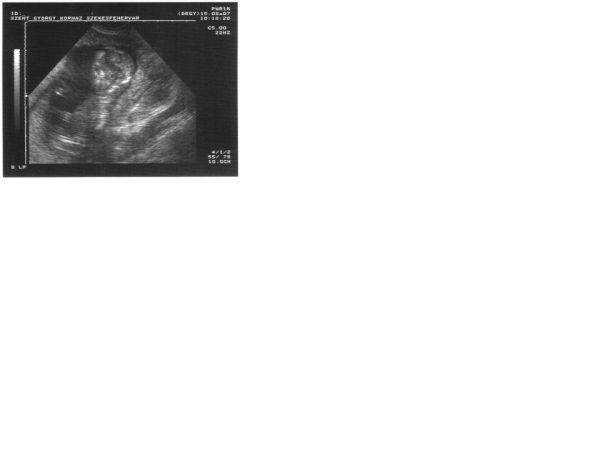

Túl vagyok a 12 hetes uh-on, a doki szerint már bőven 13 hetes a kicsike.

Íme az adatok

BPD - 23 mm

CRL - 70 mm

Tarkóredő - 1,70 mm nem tudom mi a határ, de a doki azt mondta ez jó.

Placenta - hátsófali

Orrcsont - ábrázolódik

Ritmusos szívműködés

Koponya - Szabályos kontúrú és szerkezetű

Nagyjából ez az ami lényeges.

Kaptam képet is, remélem látható belőle valami.